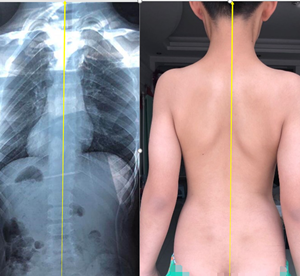

姿勢性脊柱側(cè)彎是由于不良姿勢導(dǎo)致的,通過拍片檢查,X線片顯示脊柱有偏移,cobb角度有的也超過10度,甚至有超過20度的。

姿勢性脊柱側(cè)彎又叫假性脊柱側(cè)彎,功能性脊柱側(cè)彎,是由于人體脊柱本身有側(cè)曲的功能,在拍片的一瞬間,采取了錯誤的站姿(或者平時的站姿就不好),導(dǎo)致片子上看到了側(cè)彎的存在。但測量剃刀背,度數(shù)在5度以內(nèi)(正常范圍),并沒有因椎體旋轉(zhuǎn)導(dǎo)致的肋骨變形,這樣的側(cè)彎,一般只需要觀察即可。

所以,姿勢性脊柱側(cè)彎只是脊柱在額狀面發(fā)生了偏移,并沒有在水平面發(fā)生旋轉(zhuǎn)畸形,還不是脊柱的三維畸形。這個時候就需要明確診斷,定期復(fù)查即可。不需要支具和矯形體操來干預(yù)。